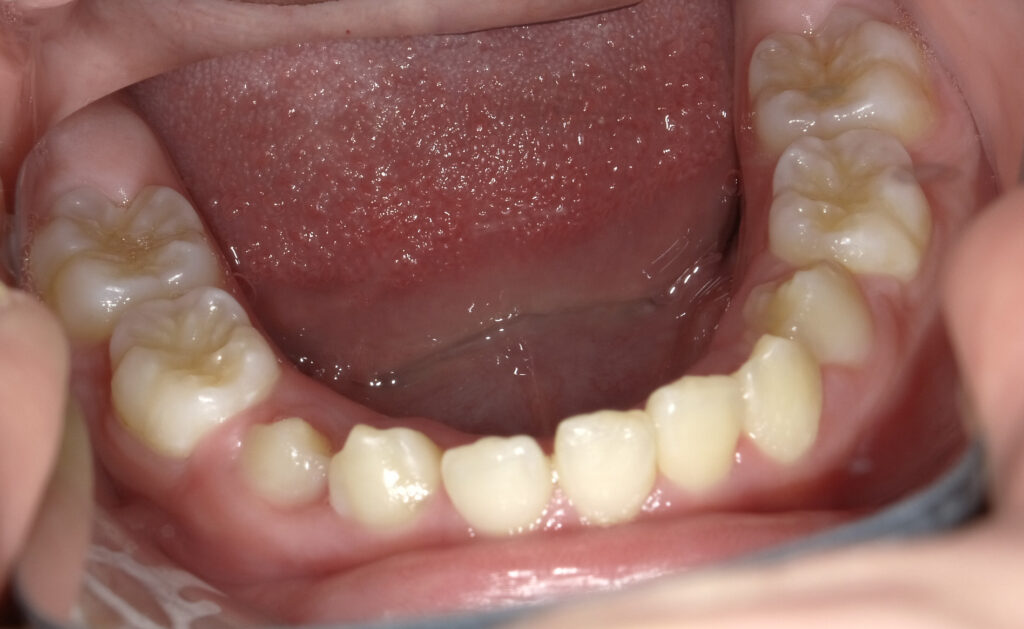

下顎

治療後